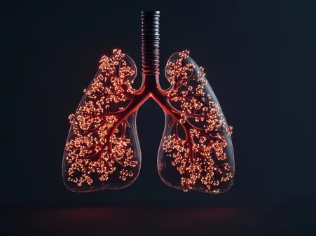

간질성 폐질환은 폐포(공기가 드나드는 작은 공기 주머니)와 폐혈관을 둘러싼 조직(간질, Interstitium)에 염증이 생기고 점차 섬유화(Fibrosis)로 진행되는 질환입니다.

- 폐 조직이 딱딱해지고(섬유화) 폐가 산소 교환을 원활하게 하지 못함

- 점진적으로 호흡곤란, 마른기침, 피로감 등의 증상이 나타남

✅ 3) 흉부 CT (고해상도 CT, HRCT)

- 폐 섬유화 진행 여부 및 염증 상태를 정밀 분석

- 간질성 폐질환 진단의 핵심 검사